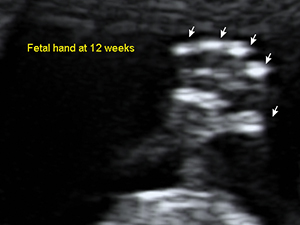

Fetal hand at 12 weeks